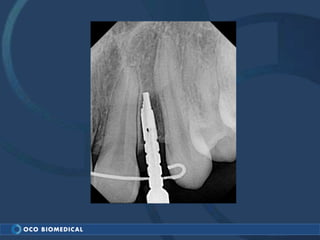

A 3.0mm dental implant was placed to replace congenitally missing maxillary lateral incisors. Dr. Tim Kosinski used a 1.8mm pilot bur and tissue punch to prepare the osteotomy site, then placed the implant by hand and seated it with a torque wrench. After ensuring the implant trajectory was within the restorative envelope, an acrylic coping was placed for temporary fabrication. At the 1 week post-op appointment, excellent soft tissue response and papilla formation were observed, and a final impression was taken to send to the lab for crown fabrication.